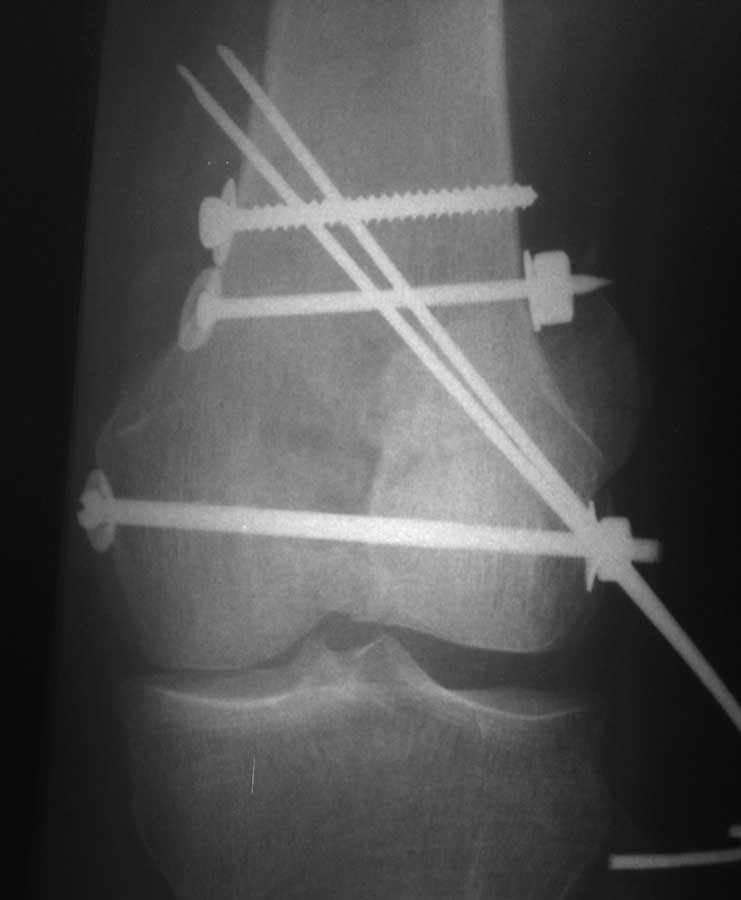

И уже лет шесть мы используем возможность ввести в дистальное овальное отверстие 3 винта, которые именно запираются в этом отверстии, не люфтят, а обеспечивают угловую стабильность - см картинку.

Получается и стабильно, и очень дистально, нижний край отверстия в 3 мм от дистального конца гвоздя.

С моей точки зрения, безусловная ценность предложенного Вами, Александр Николаевич, стержня состоит в возможности введения блокирующих винтов максимально близко к суставной поверхности дистального отломка, что значительно расширяет показания для применения интерлокинга. Можно предположить, что в техническом плане таким образом ввести блокирующие винты является непростой задачей. Кроме того, все они расположены в одной плоскости на небольшом расстоянии друг от друга.

Мне представляется, что конструкция с максимальными прочностными характеристиками будет иметь вид предложенной во вложенном файле. Такую конфигурацию расположения блокирующих отверстий на дистальном конце имеет стержень для большеберцовой кости фирмы ChM. Для бедренной кости такой стержень мне неизвестен. Поэтому в необходимых случаях (хорошо, что такие случаи встречаются не часто), как вариант, мы используем custom made стержень.

Позволю себе напомнить коллегам ещё раз, что являюсь сторонником антеградного остеосинтеза при переломах дистального эпиметафиза бедренной кости. Такая приверженность основана не на преимуществах внесуставного введения стержня или большем проценте положительных результатов. Она основана на возможности обеспечить блокирование на минимальном расстоянии от суставной поверхности в нескомпрометированной кости и, таким образом стабилизировать максимально низкие переломы. В приведенном Вами случае самый дистальный из блокирующих винтов проведен на расстоянии более 2 см от конца стержня. Из-за того, что к стержню присоединяется кондуктор, на стержне теряется 1-1,5 см его длины, где можно было разместить отверстия для блокирования. И что более важно, вместе с потерянной для этой цели длиной стержня утрачивается для размещения блокировочных винтов, пожалуй, самая ценная часть дистального эпиметафиза бедренной кости. Проблемы дистального блокирования в разных плоскостях, локализации точки ввода стержня при антеградном остеосинтезе – это всё решаемые технические проблемы. Но антеградный остеосинтез низких дистальных переломов бедра при адекватном блокировании в нескомпрометированной кости обеспечивает решение стратегической задачи – стабильный остеосинтез и возможность нагрузки.

Наш гвоздик, выпускаемый предприятием ЦИТО, тоже скорее из универсальных, хотя и с расширенными возможностями для дистальных переломов. Это овальное отверстие внизу задумывалось как динамическое для высоких переломов, очень дистально его разместили, чтобы не опасаться перелома гвоздя по этому отверстию. А возможность вот такого введения винтов, образующих "сборный клинок", обнаружилась года через 3 его применения.

положительных результатов. Она основана на возможности обеспечить блокирование на минимальном расстоянии от суставной поверхности в нескомпрометированной кости и, таким образом стабилизировать максимально низкие переломы.

Но практика показывает, что классификации существуют не зря, и стоит пользоваться ими, а не ориентироваться на абстрактные "максимально низкие переломы". Подавляющее большинство поступающих к нам больных с дистальными переломами - это C1 и С2. И показанный в прошлом сообщении гвоздик прекрасно справляется. Наверно, сгодятся и многие современные гвозди разных производителей, типа RAFN Synthes. А вот при настоящих C3 одним гвоздем не обойтись, нужны как минимум винты мимо, а то и введение на одном уровне нескольких винтов и/или спиц веером...

В приведенном Вами случае самый дистальный из блокирующих винтов проведен на расстоянии более 2 см от конца стержня.

На этом большеберцовом стержне центр ближайшего к кондуктору отверстия в 14 мм от конца. И пример был про то, что пластина тут, скорее всего, была бы не худшим выбором.